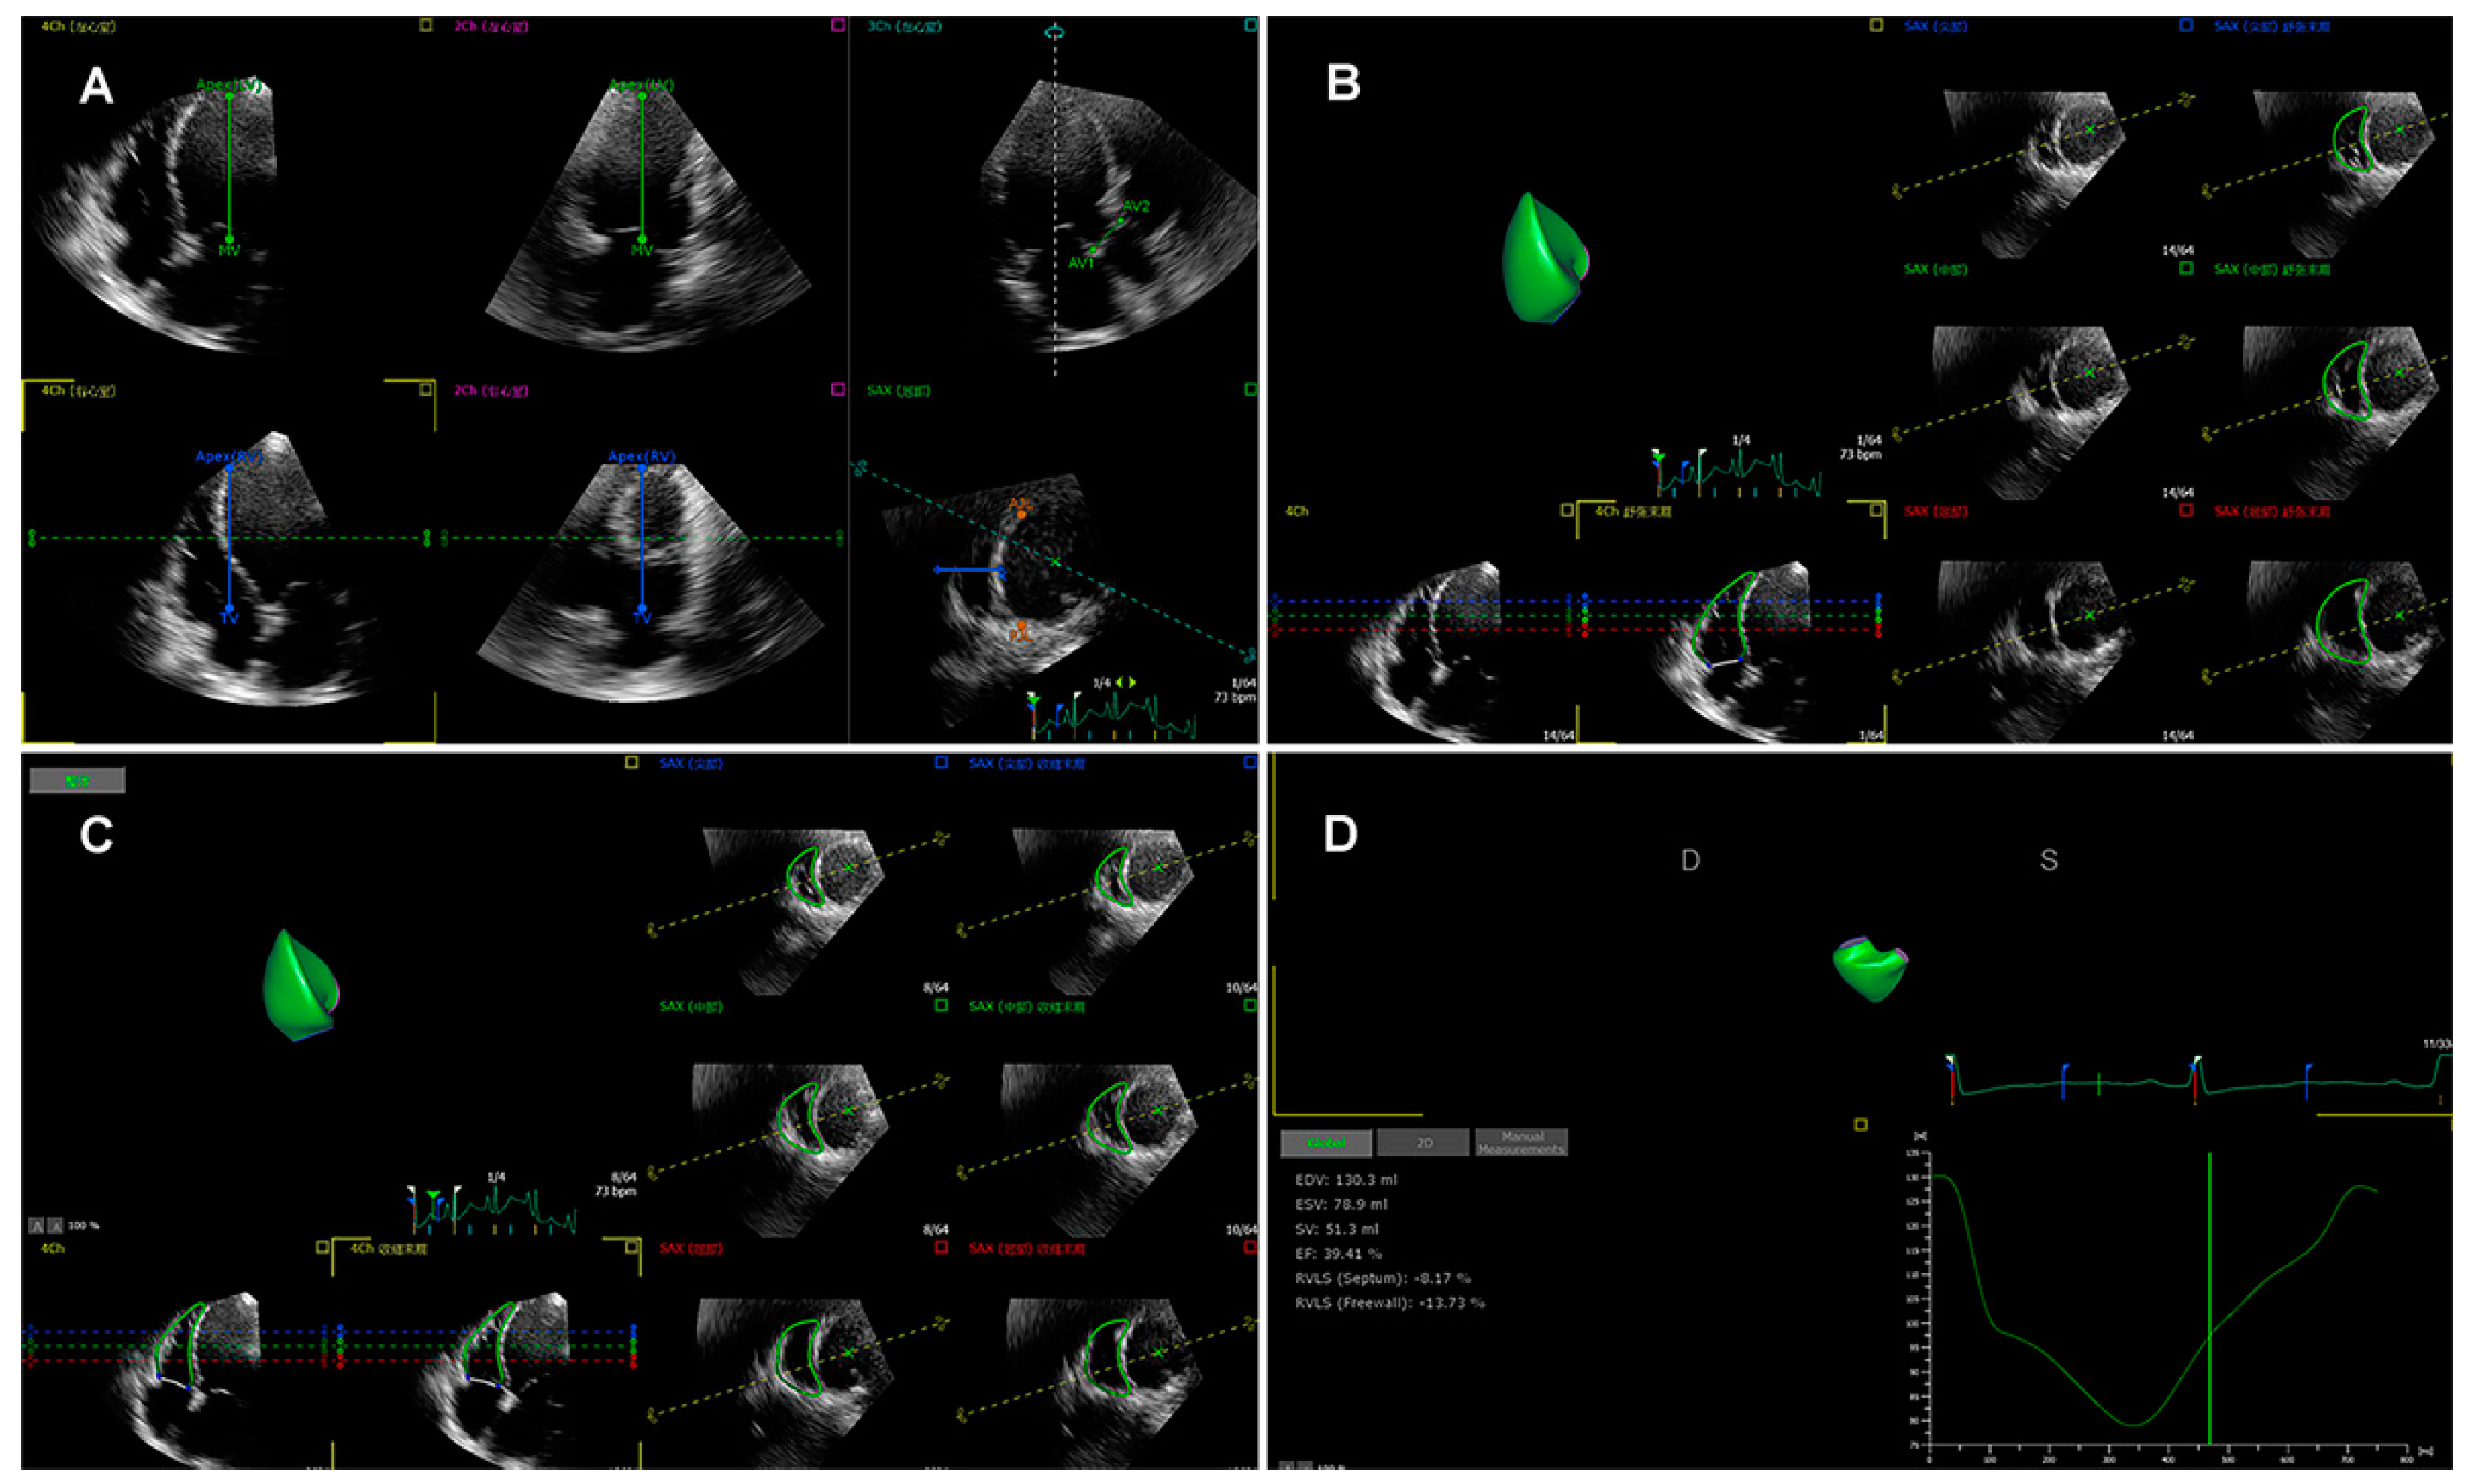

More recently, three-dimensional speckle tracking echocardiography (3D-STE) has been introduced as a novel technique than can track the myocardial motion within the 3D volume. Thus, 3D-STE is free of geometric assumptions and out-of-plane motion of the speckles, allowing a more accurate and comprehensive evaluation of myocardial function owing to overcoming the limitations of 2D-STE [35,38,65,66]. Three-dimensional STE analysis for the right ventricle is shown in Figure 2. Its accuracy and reproducibility in assessing RV function have been confirmed in patients with transplanted hearts, pulmonary hypertension, and hypoplastic left heart syndrome after Fontan palliation [63,67,68,69]. Moreover, we previously investigated the feasibility and accuracy of 3D-STE for the quantification of RVLS in comparison with CMR imaging in a large number of study populations with a wide variety of RVEF and cardiovascular pathologies, and found that the 3D-RVFWLS values correlated better than 2D-RVFWLS values with CMR values (0.85 vs. 0.64) with smaller bias and narrower limits of agreement. Our findings demonstrated the superiority of 3D-RVFWLS over 2D-RVFWLS in evaluating RV function against CMR imaging [70,71]. However, 3D-STE also has several limitations, such as low temporal resolution and dependence on image quality [35,64].

Figure 2. Longitudinal strain of the RV free wall and septum using three-dimensional speckle tracking echocardiography. (A) Setting reference points; (B,C) RV endocardial border tracking; (D) Longitudinal strain of RV free wall and septum were automatically generated.